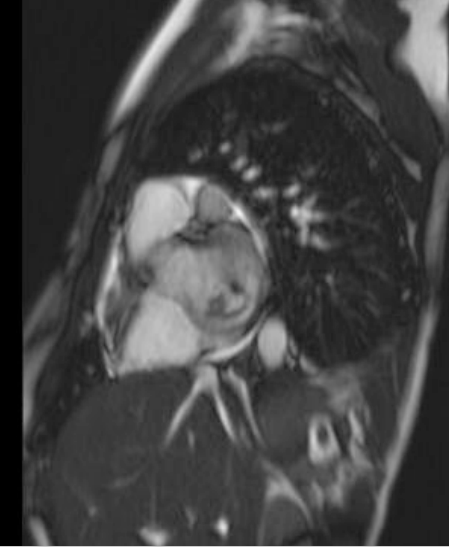

Case Presentation: A 17 year old male recently diagnosed with high risk B-Precursor ALL and induction failure, was found in clinic to have an acute murmur. Three days prior, he had arm and leg aches, dry cough, a single fever and fatigue that improved with blood transfusion. Now he had a 3/6 holosystolic blowing murmur at his cardiac apex. TTE a month ago was normal. His ANC was 332. He received his chemotherapy and was admitted. TTE now showed moderate mitral regurgitation, low normal ejection fraction and a 12mm vegetative mass on the anterior mitral leaflet.

The working differential included thrombus, infectious vegetation or leukemic infiltrate. He had no infectious symptoms and the mass lacked typical vegetation features, so endocarditis was low on the differential. The location of the mass, normal LV function and lack of arrhythmias made clot less likely. Given his failed induction, the mass was thought to be leukemic infiltrate. Blood cultures were negative, and he had no endocarditis stigmata or infectious symptoms. He was seen by Infectious Disease and Cardiology; the mass was stable on TTE. He was discharged with follow up.

Two days later, he returned with right facial numbness and dysarthria and was found to have a right cerebellar stroke. TTE showed the mass to be larger and more mobile. A DNA sequencing culture from his prior admission was positive for Aspergillus. His B-1,3-D-glucan level was elevated. A CT chest showed nodular opacities consistent with fungal infection. An US of his right arm showed a septic abscess. He was diagnosed with Aspergillus endocarditis and valvulopathy with embolic features. He was started on micafungin and voriconazole. Due to induction failure, he was not a candidate for cardiovascular surgery. His B-1,3-D-glucan level downtrended. He sustained a second Left MCA stroke, emboli to his extremities, erosion of his pulmonary artery, and passed away three months after initial presentation.